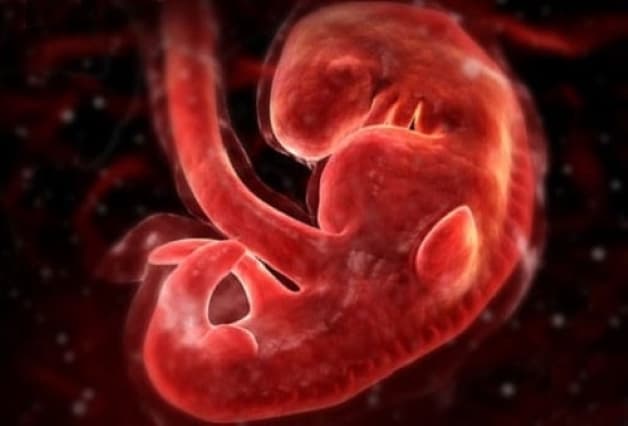

Việc chụp X quang khi mang thai 2 tuần thì điều này lại càng nguy hiểm hơn. Bởi vì lúc này thai nhi vẫn chưa được hình thành mà đang ở dạng trứng vừa mới gặp được tinh trùng và chưa làm tổ ở buồng tử cung. Đây mới chỉ được xem là giai khởi điểm đầu tiên cho một thai kỳ. Cũng chính bởi vậy mà sự nhạy cảm với tịa bức xạ lại càng tăng lên.

Mức độ ảnh hưởng của tia X sẽ phụ thuộc vào từng giai đoạn phát triển của thai nhi. Thai nhi càng bé thì khả năng bị ảnh hưởng càng lớn.

– Với thai nhi từ 0-1 tuần tuổi: Tia X có thể sẽ làm chết phôi thai.

– Với thai nhi từ 2-7 tuần tuổi: Tia X có thể gây dị dạng, khiến cho thai nhi tăng nguy cơ mắc dị tật bẩm sinh và có nguy cơ mắc ung thư.

– Từ tuần thứ 20 trở đi: Tia X sẽ không làm ảnh hưởng nhiều tới thai nhi, bởi lúc này cơ thể của em bé đã gần như phát triển hoàn thiện.

Thai nhi trong 3 tháng đầu tiên của thai kỳ được xem là giai đoạn vô cùng nhạy cảm khi mà nguy cơ sảy thai luôn thường trực nếu như mẹ có bất kỳ hoạt động hay tác động mạnh nào vào cơ thể. Tia X khi tác động vào cơ thể mẹ trong thời điểm mang thai khi em bé được 2 tuần tuổi được xem là ít gây ra tác động nhất là với cường độ dưới 5 rad.

Tia X có thể làm chết phôi thai khi thai nhi mới chỉ 2 tuần tuổi